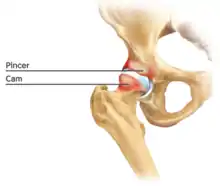

Cam-type femoroacetabular impingement

Cam impingement is created by the abnormal development of the femoral head-neck junction causing what has previously been described as a 'pistol-grip deformity'. This type of deformity is characterised by varying amounts of abnormal bone on the anterior and superior femoral neck at the head-neck junction (see fig. 6). The head-neck junction is at the base of the ball of the hip, where it joins the short neck, which in turn carries on downwards into the femur, or thighbone, itself. A bony protrusion or bump at the head-neck junction has been likened to a cam, an eccentric part of a rotating device. This leads to joint damage as a result of the non-spherical femoral head being forced into the acetabulum mainly with flexion and/or internal rotation. This may impart compression and shear forces to the articular cartilage, and may lead to labral tears and peeling away of the articular cartilage from the underlying bone, so-called cartilage delamination (see fig. 8).[9][10]

Pincer-type femoroacetabular impingement

In contrast, pincer impingement is a result of an abnormality on the acetabular side of the hip joint.[2] The acetabulum may either have a more posterior orientation than normal, otherwise known as acetabular retroversion (seen as the crossover sign on AP radiographs), or there may be extra bone around the rim. This results in contact of the femoral neck against the labrum and rim of the acetabulum during hip movement earlier than might otherwise be the case. Repeated contact between the femoral neck and the edge of the acetabulum may lead to damage to the labrum and adjacent articular cartilage. Bone formation, or ossification within the labrum may be commonly seen as a result of this repeated contact. It is thought that this type of impingement may also predispose to the development of osteoarthritis.

The goal of the arthroscopic treatment of pincer impingement is to reduce the acetabular over coverage of the hip. Methods to reduce this over coverage of the ball by the socket include labral detachment or peel back, acetabular rim trimming using burrs, often reattaching the labrum with anchors at the end of the procedure. With the exception of cases of severe global over coverage of the hip, or situations in which the existing labrum has turned to bone (or ossified), excessive acetabular rim resection should be avoided in order to prevent iatrogenic increases in hip joint contact pressures.[14]